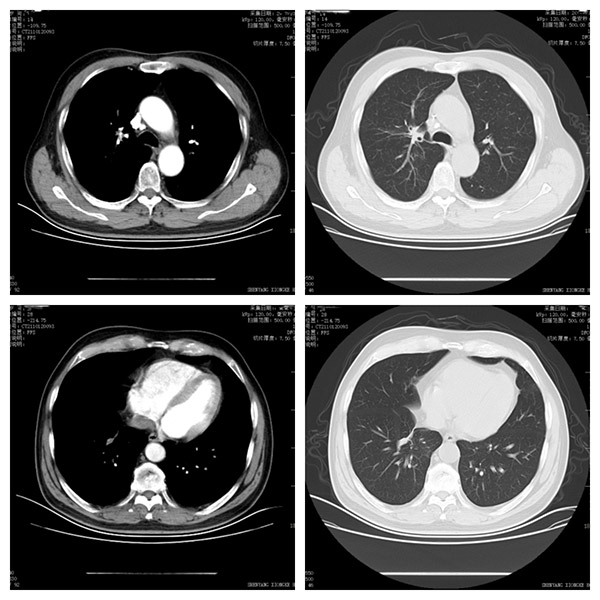

术后CT

术后老许大爷积极配合治疗,等到2个月左右再次复查CT时,老许大爷和家属发现右肺上下叶两个病灶“神奇”的消失了。转移不可怕,精准抗癌路,我们遵循患者个性化的治疗方案,一患一案,始终为患者制定符合自身情况的治疗方案,让患者有信心、积极的面对肿瘤。